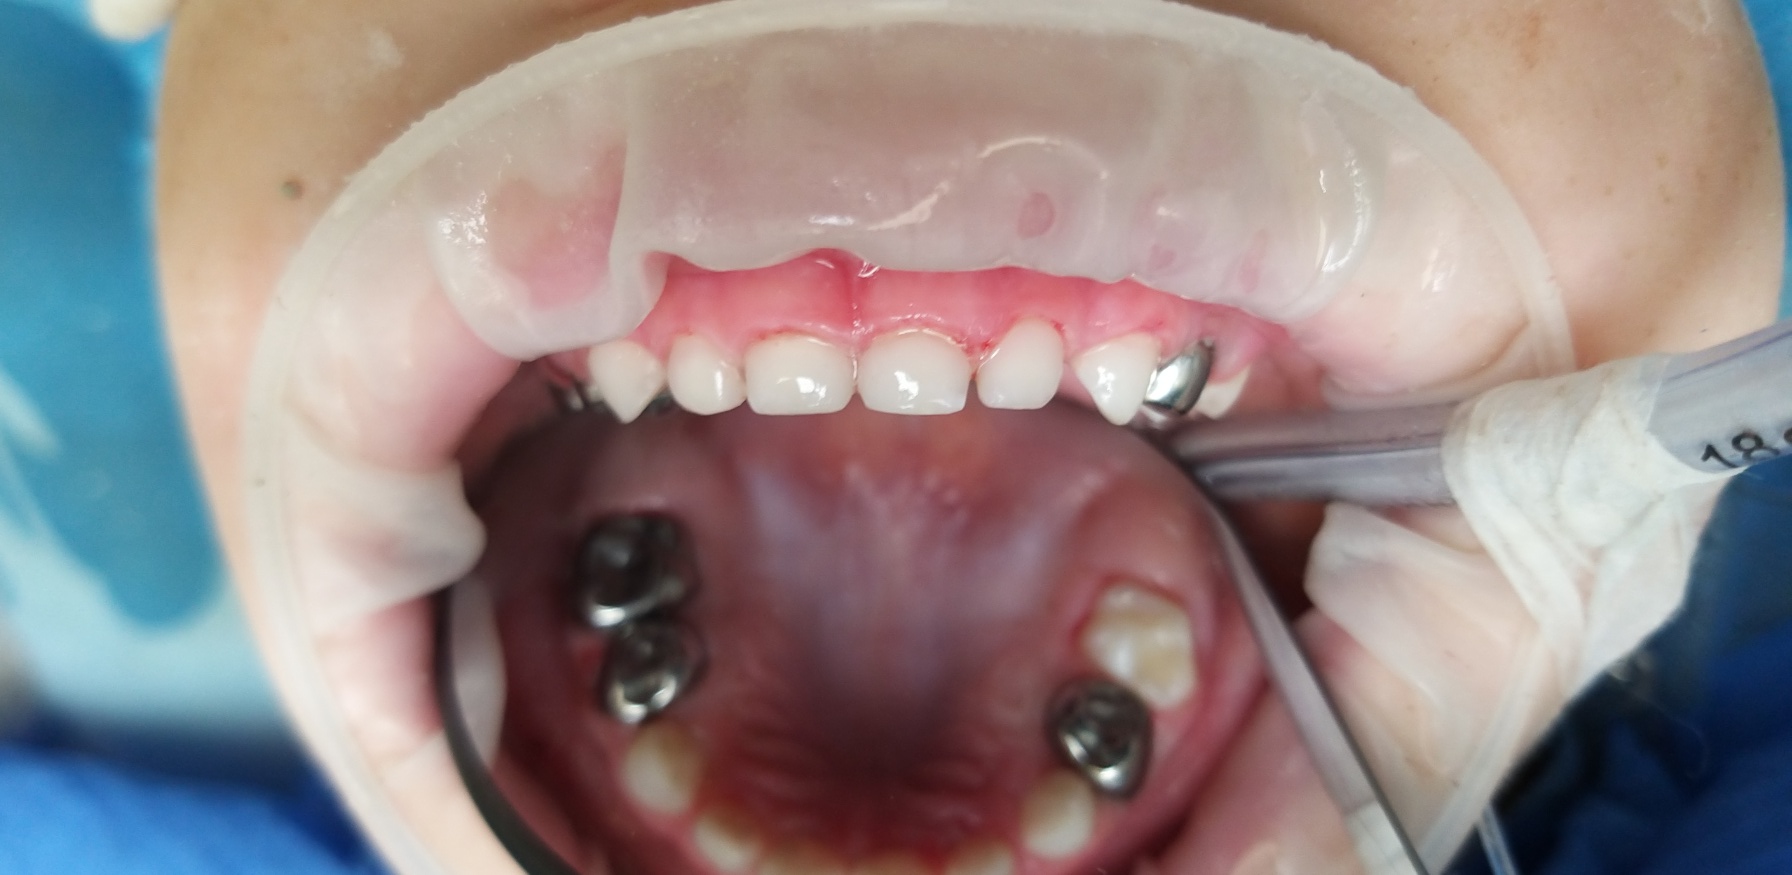

Стартувавши у 2009 році як одна з перших приватних клінік у Борисполі, «Здорова усмішка» і до сьогодні впевнено утримує позиції лідера на ринку стоматологічних послуг. Все це завдяки багаторічному досвіду, дотриманню чітких стандартів якості та постійному впровадженню інновацій. Свідченням цього є усмішки не лише киян, а й пацієнтів з багатьох країн світу.

Час не стоїть на місці, і ми впевнено крокуємо разом з ним. Щороку з’являються дієві методики та нові підходи, сучасні матеріали, які ми активно застосовуємо в процесі лікування. Аби забезпечити найвищий рівень послуг, ми постійно вдосконалюємось та навчаємось, беручи активну участь в різних галузевих виставках, семінарах та конференціях.

Ми працюємо тільки з найкращими матеріалами: Нанокомпозити Filtek виробництва США.